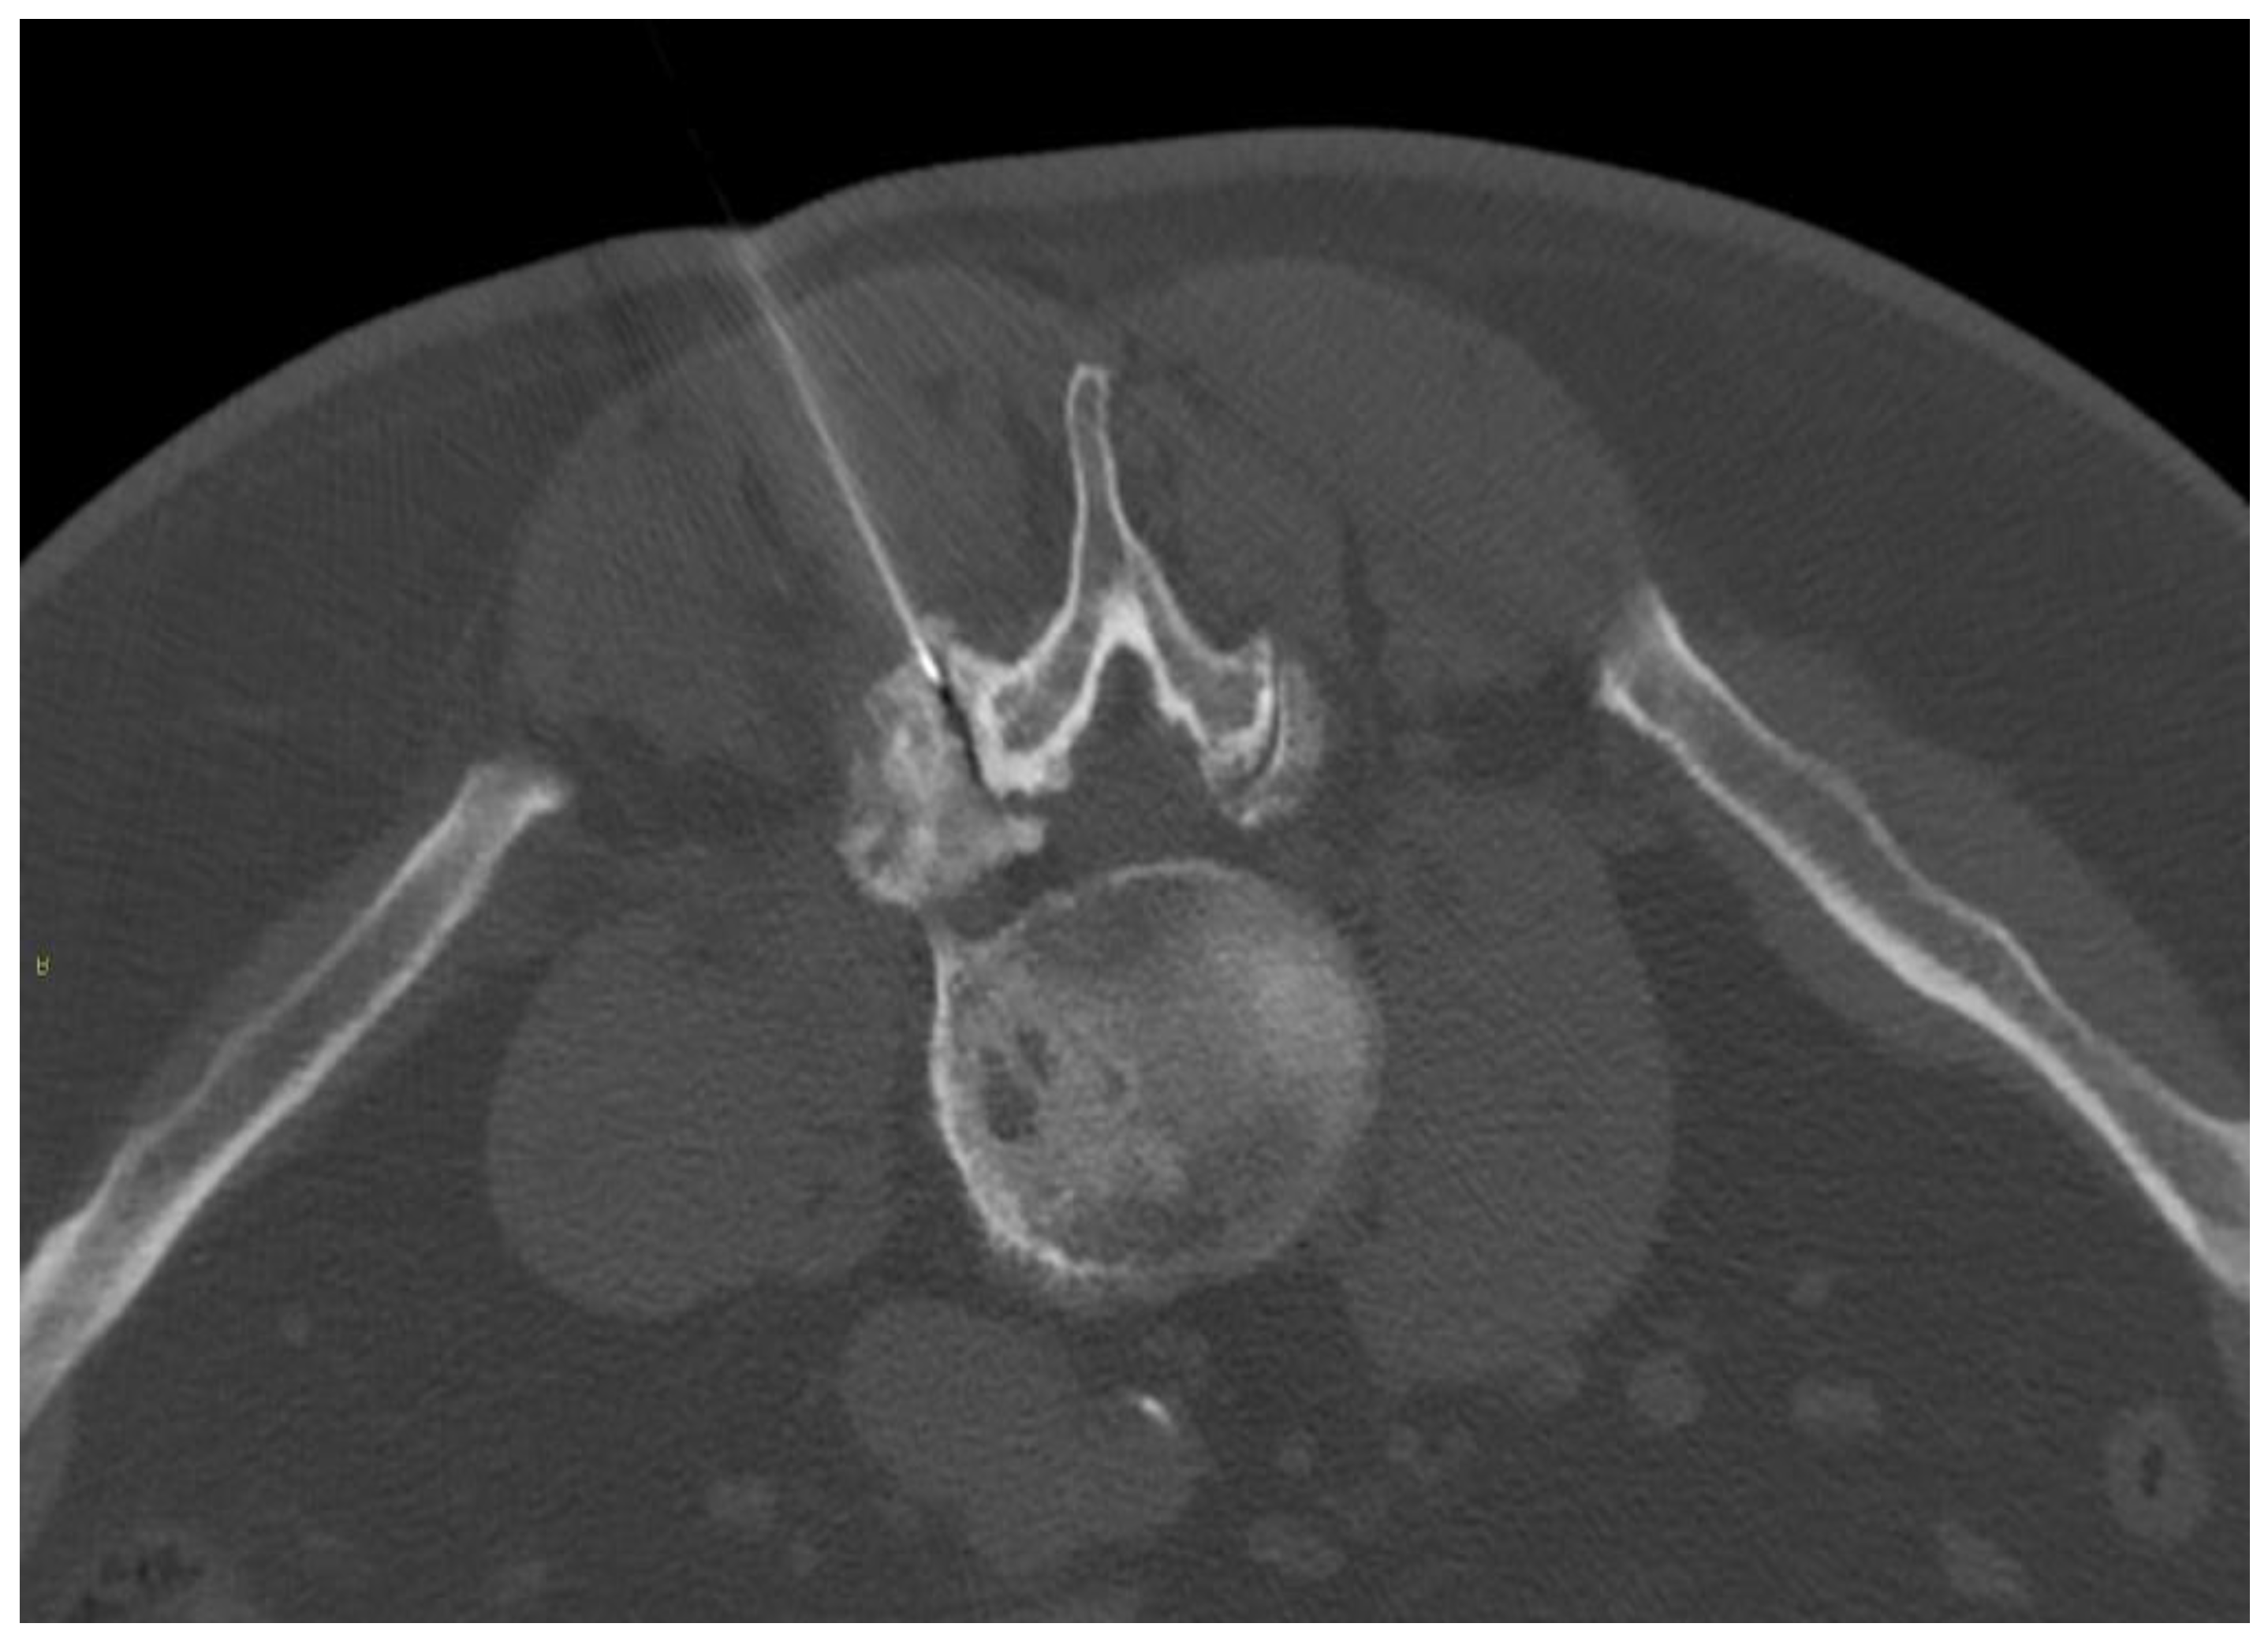

The inferior process of the superior vertebrae and the superior process of the inferior vertebrae are the articular facets, which form a synovial articulation, also called a zygapophysial joint. In a prone position, a posterior approach can reach the joint capsule and puncture it with a needle (Figure 6), although a peri-articular injection may alleviate pain as well as an intra-articular injection [59].

Figure 6.

A 67-year-old male with severe lumbar facet joint arthritis underwent CT-guided L5-S1 right posterior joint corticosteroid injection.